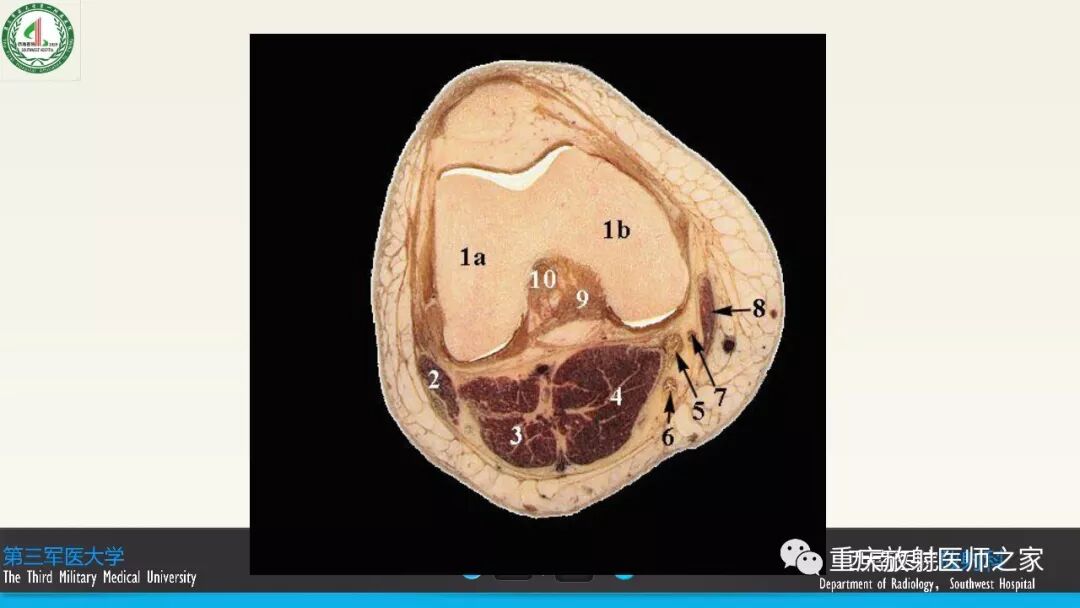

图文详解膝关节韧带的解剖及诊断